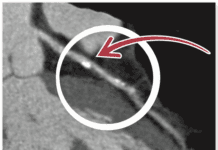

Microvessel disease is caused by endothelial dysfunction, which means that arteries too small to be stented or bypass constrict when they should dilate. Patients with microvessel disease have normal cardiac catheterizations (no blockages seen), but have chest pain with exercise or stress. The test we like to do to diagnose microvessel disease is cardiac MRI.